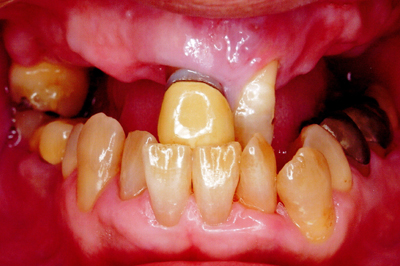

治療例2

歯ぐきが安定した状態

土台をたてた

噛める機能を回復

| ご費用 | 手術費用人工歯根 1本275,000円(税込) 上部構造 88,000円~110,000円(税込) |

|---|---|

| リスク・副作用 | 保険非適応(自費診療) 特定の全身疾患や持病のある方、顎骨密度の足りない方、妊娠中の方は手術ができない場合があります。 下顎のインプラント手術の際、偶発症のリスクがあります。 人工歯根が顎骨と癒着しないリスクがあります。 インプラント周囲炎になるリスクがあります。 |